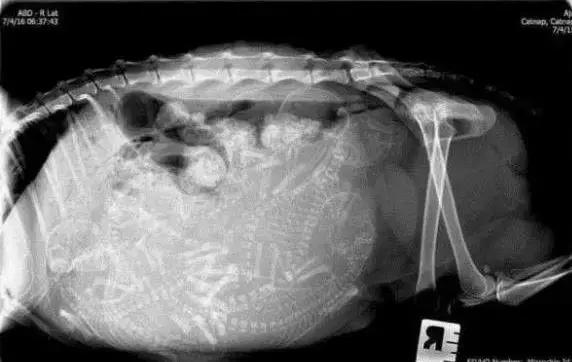

X光检查

怀孕大约45天时,就可以做X光检查了。小猫的骨架都可以看得清清楚楚。兽医师一般会做两个X光检查,来确定小猫的数量,并且查找潜在的问题。

这种X光检查不会伤害母猫和小猫。虽然X光检查的准确率也不到100%,但是,数胎儿数量的话,X光比超声波更好。